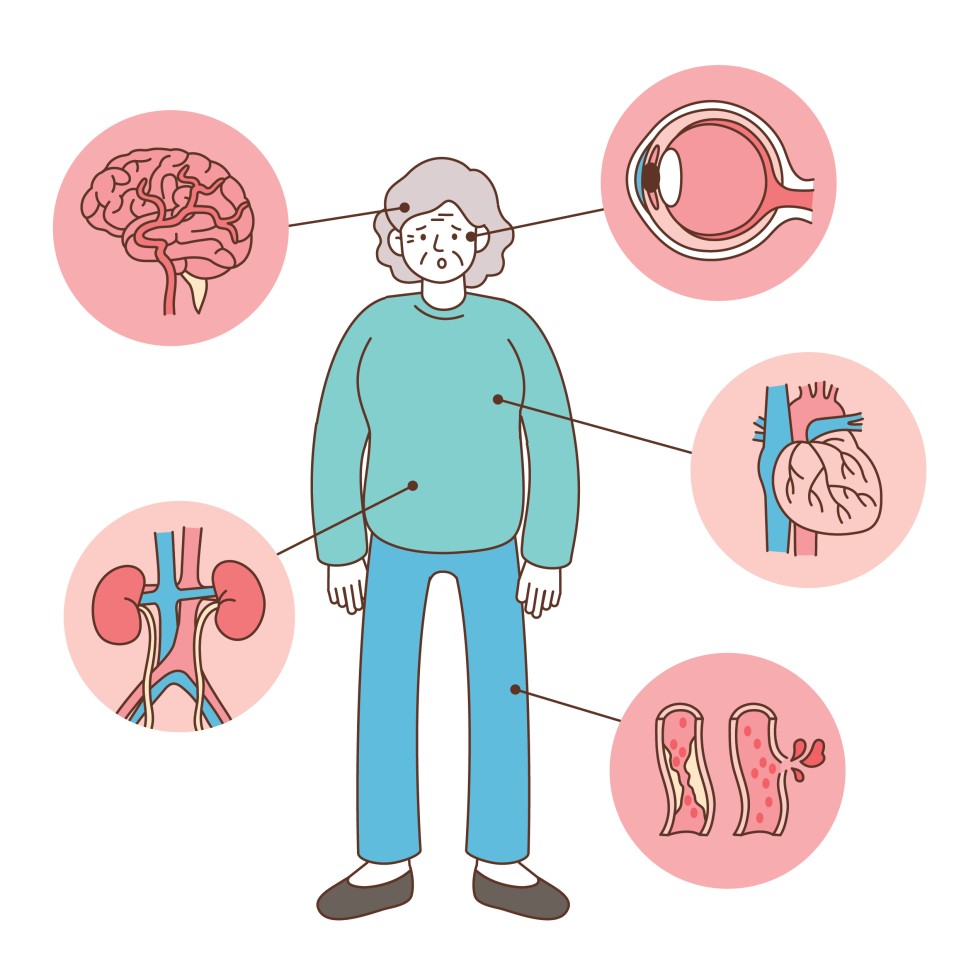

고혈압이 있으면 심장에 부담이 커지고 혈관도 손상되게 됩니다.또한 신장이나 뇌에 혈액을 공급하는 혈관의 변화는 그 장기의 기능에 영향을 미쳐 다양한 합병증이 나타납니다.

고혈압 합병증의 종류

뇌졸중, 혈관성 치매

고혈압 망막증

단백뇨, 만성콩팥병

심근경색, 심부전, 협심증